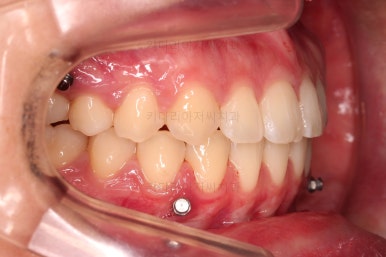

장치를 부착했는데요.

윗니는 웃을 때 더 많이 보이기 때문에 세라믹 장치를 선택하셨고, 아랫니는 거의 안보이는 타입이셔서 메탈장치로 부착을 했습니다.

위아래 둘 다 자가결찰 장치였고요.

동일 회사의 장치였으며 단지 재질만 메탈이냐 세라믹이냐의 차이가 있었던거죠.

이렇게 위아래는 설측이든 뭐든 메탈이든 세라믹이든 마음대로 섞을 수 있습니다.